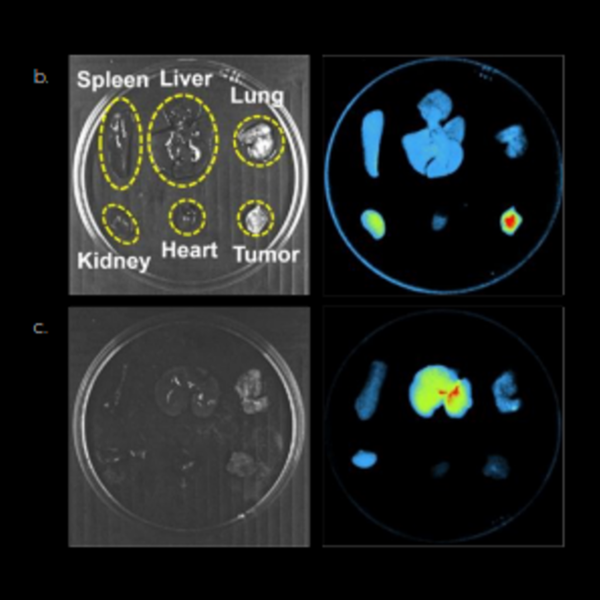

3D optical tomography

An integrated 3D tomography module reconstructs bioluminescent signals in 3D and overlays them onto a topographical model of the imaging subject.

To better understand anatomical and deeper tissue features, the mouse organs and bones can be superimposed onto the topographical model using the digital organ and bone library.

Spleen, Liver, Lung, Kidney, Heart, Tumor. Image Credit: Scintica Instrumentation Inc

Biodistribution studies

In preclinical biodistribution research, optical imaging offers a distinct benefit due to its ability to view the entire body; a single image can measure several organs throughout the body.